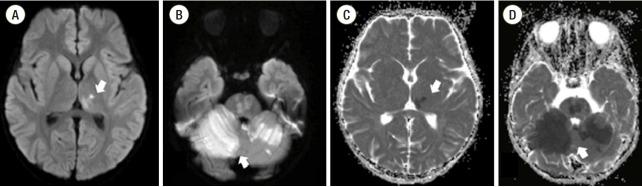

Acute cerebral infarctions are rare in children, however they can occur as a complication of a (MP) infection due to direct invasion, vasculitis, or a hypercoagulable state. We report on the case of a 5-year-old boy who had an extensive stroke in multiple cerebrovascular territories 10 days after the diagnosis of MP infection. Based on the suspicion that the cerebral infarction was associated with a macrolide-resistant MP infection, the patient was treated with levofloxacin, methyl-prednisolone, intravenous immunoglobulin, and enoxaparin. Despite this medical management, cerebral vascular narrowing progressed and a decompressive craniectomy became necessary for the patient's survival. According to laboratory tests, brain magnetic resonance imaging, and clinical manifestations, the cerebral infarction in this case appeared to be due to the combined effects of hypercoagulability and cytokine-induced vascular inflammation.

急性脑梗死在儿童中较为罕见,然而,它可能作为支原体(MP)感染的并发症出现,原因包括直接侵袭、血管炎或高凝状态。我们报告了一例5岁男孩的病例,该男孩在诊断为MP感染10天后,在多个脑血管区域发生了广泛的中风。基于脑梗死与大环内酯耐药MP感染相关的怀疑,该患者接受了左氧氟沙星、甲泼尼龙、静脉注射免疫球蛋白和依诺肝素治疗。尽管采取了这种治疗措施,脑血管狭窄仍在进展,为了患者存活,进行减压颅骨切除术成为必要。根据实验室检查、脑磁共振成像和临床表现,该病例中的脑梗死似乎是由于高凝状态和细胞因子诱导的血管炎症的联合作用所致。